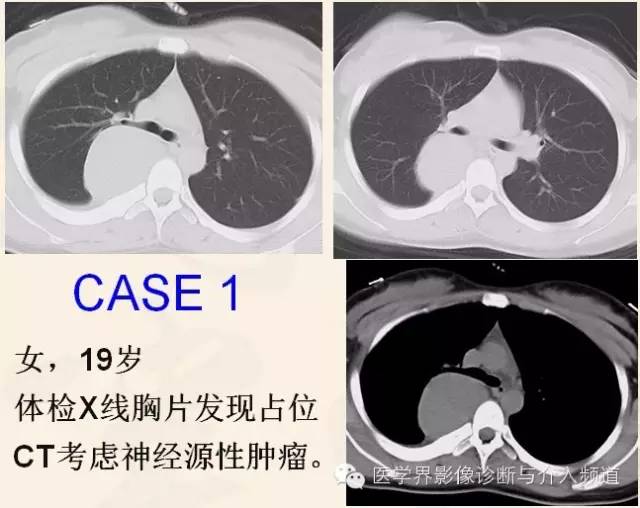

胸腺瘤(Thymoma)

来源于胸腺上皮细胞的肿瘤,发病年龄多在40岁以上,是前纵隔常见的肿瘤,可以局部外侵、播散、复发和远处转移。

近期WHO依胸腺瘤的上皮细胞形态及其与淋巴细胞比例,将其分为A型、AB型、B型和C型,该分型可作为独立预后因素,并与肿瘤侵袭性、复发等密切相关。

CT表现

良性胸腺瘤:多为圆形或类圆形实质性肿块,有包膜,边界光滑,密度均匀,增强扫描轻至中度强化,与周围组织结构分界清晰,周围脂肪间隙显示良好,肿瘤与邻近结构之间通常有一低密度透亮带。